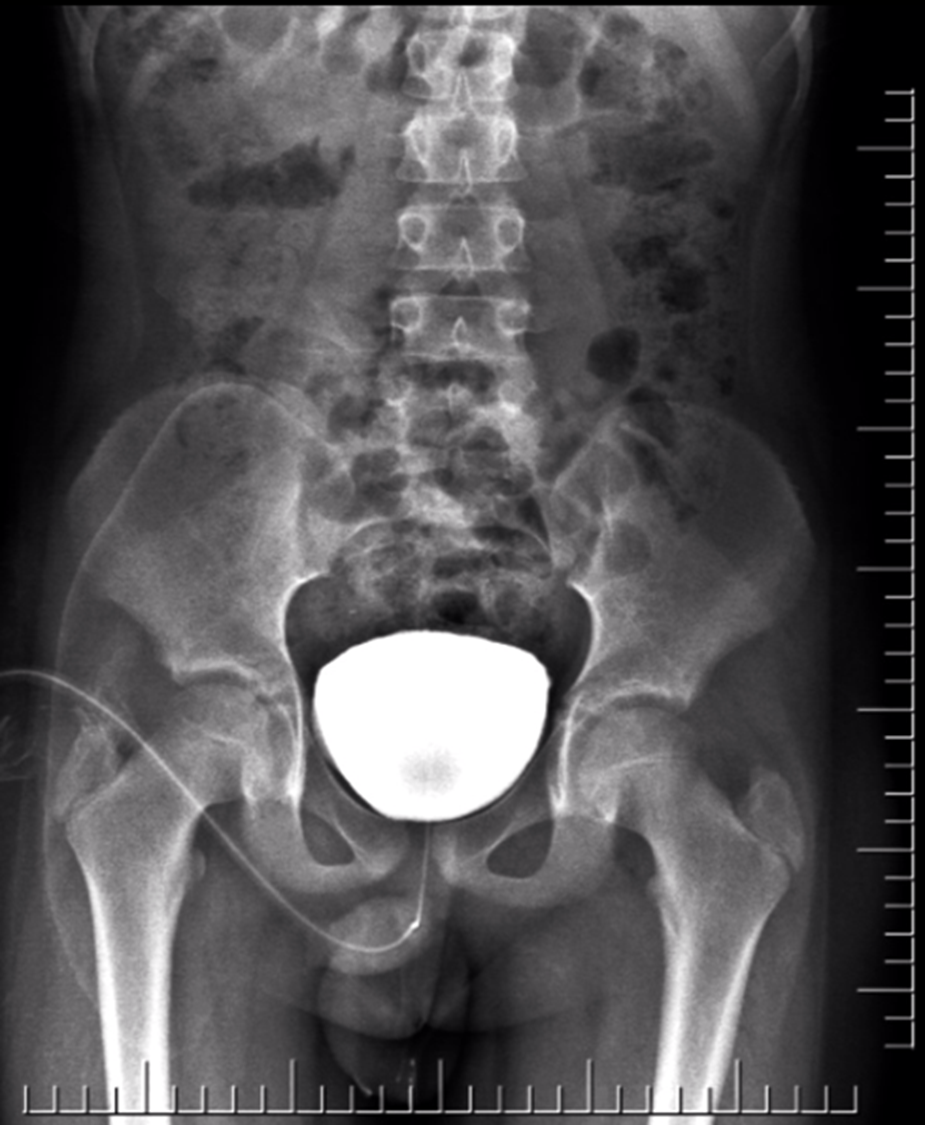

Cystogram

Indications - Cystitis - Trauma - Tumors - Congenital anomalies

Two route of filling the bladder

As part of IVU

- Catheterization and filling the bladder with contrast Cystogram

Micturating cystourethrogram

Functional and anatomical evaluation of bladder and urethra. Typically for kids with recurrent UTI